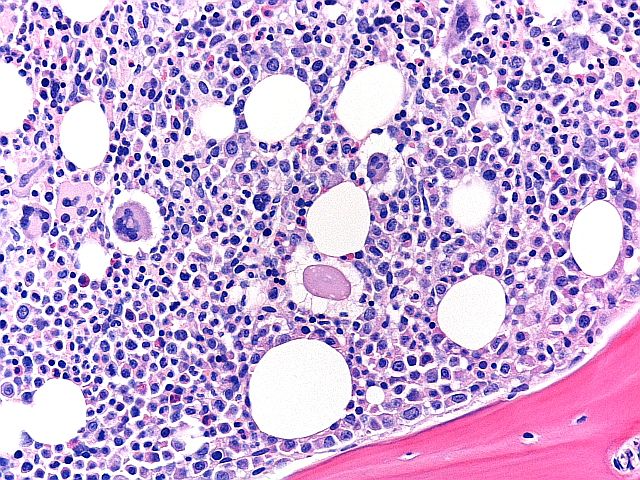

H&E - BMT-regeling

Dit is een uitstekende voorbereiding op een BMT-biopsie, met een evenwichtige H&E-kleuring, goede chromatinedetails en selectieve kleuring van celtypen in het beenmergweefsel. Deze slide kreeg een 9/10 bij de beoordeling.